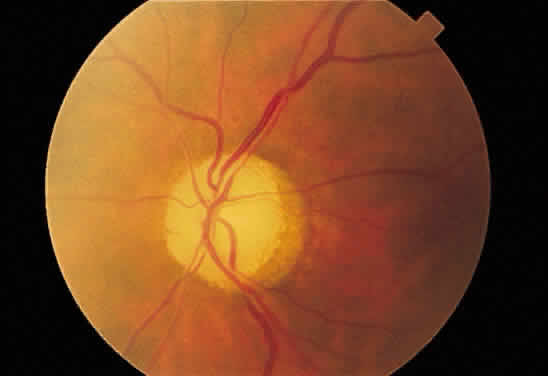

Fig. 30. A. Photomicrograph of an optic disc with papilledema. There is edema of the

disc surface, some engorgement of the vessels, and lateral displacement

of the photoreceptor elements, which results in enlargement of the

blind spot in papilledema. B. Early papilledema in a patient with pseudotumor cerebri. The disc margin

is blurred, the surface slightly elevated, and a small hemorrhage is

present superiorly. (A, courtesy of Ralph C. Eagle Jr, MD, Philadelphia, PA) Fig. 30. A. Photomicrograph of an optic disc with papilledema. There is edema of the

disc surface, some engorgement of the vessels, and lateral displacement

of the photoreceptor elements, which results in enlargement of the

blind spot in papilledema. B. Early papilledema in a patient with pseudotumor cerebri. The disc margin

is blurred, the surface slightly elevated, and a small hemorrhage is

present superiorly. (A, courtesy of Ralph C. Eagle Jr, MD, Philadelphia, PA)